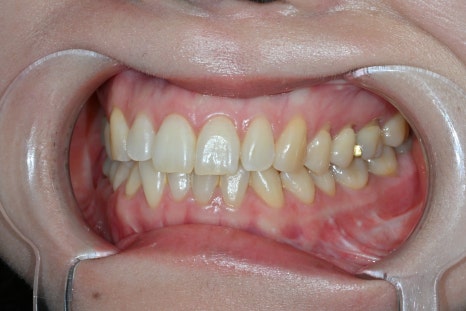

A real case that started with an Obzero consultation

This patient visited us wanting to improve their image naturally.

Rather than simply making the teeth brighter,

✔ subtle coloring

✔ a neat tooth arrangement

✔ a smile that suits the face

were requested, and accordingly,

treatment was performed with 8 Obzero Pure Laminates.

In this case as well,

a color tone similar to natural teeth was achieved.

Obzero Pure is

a treatment that expresses "light and depth" rather than color alone.